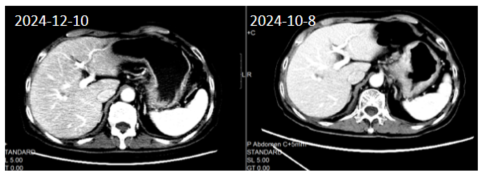

患者定期复查(图3),疗效评价为部分缓解(PR)(腹膜后多发肿大淋巴结从15mm缩小到5mm)。